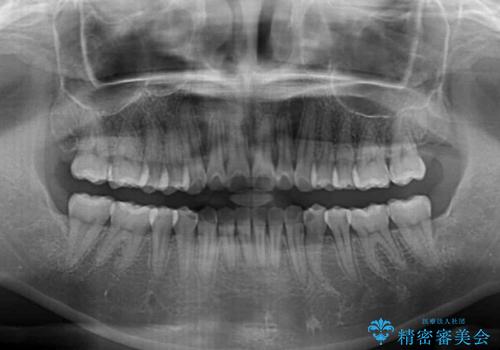

- 上下前歯のデコボコを気にして来院された患者様です。

インビザラインによる上下歯列の拡大と、IPR(歯と歯の間を削る)にるスペースの獲得により、前歯のデコボコを改善することとしました。

しっかりと装着時間を遵守してくださったので、思い通りの歯列に整えることができました。

結婚式前に終了させることができ、患者様には大変満足していただきました。